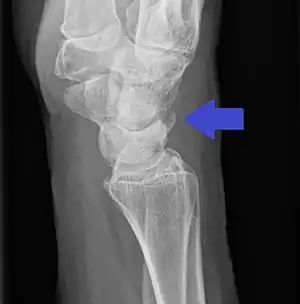

Triquetral fracture indicated by the white arrow.

Triquetral fracture as seen on lateral view of a radiograph.

Triquetral fractures can occur due to forceful flexion of the wrist, causing an avulsion of the dorsal aspect of the bone that is often hidden on anterior radiographs, but can be seen as a tiny bone fragment on lateral views.